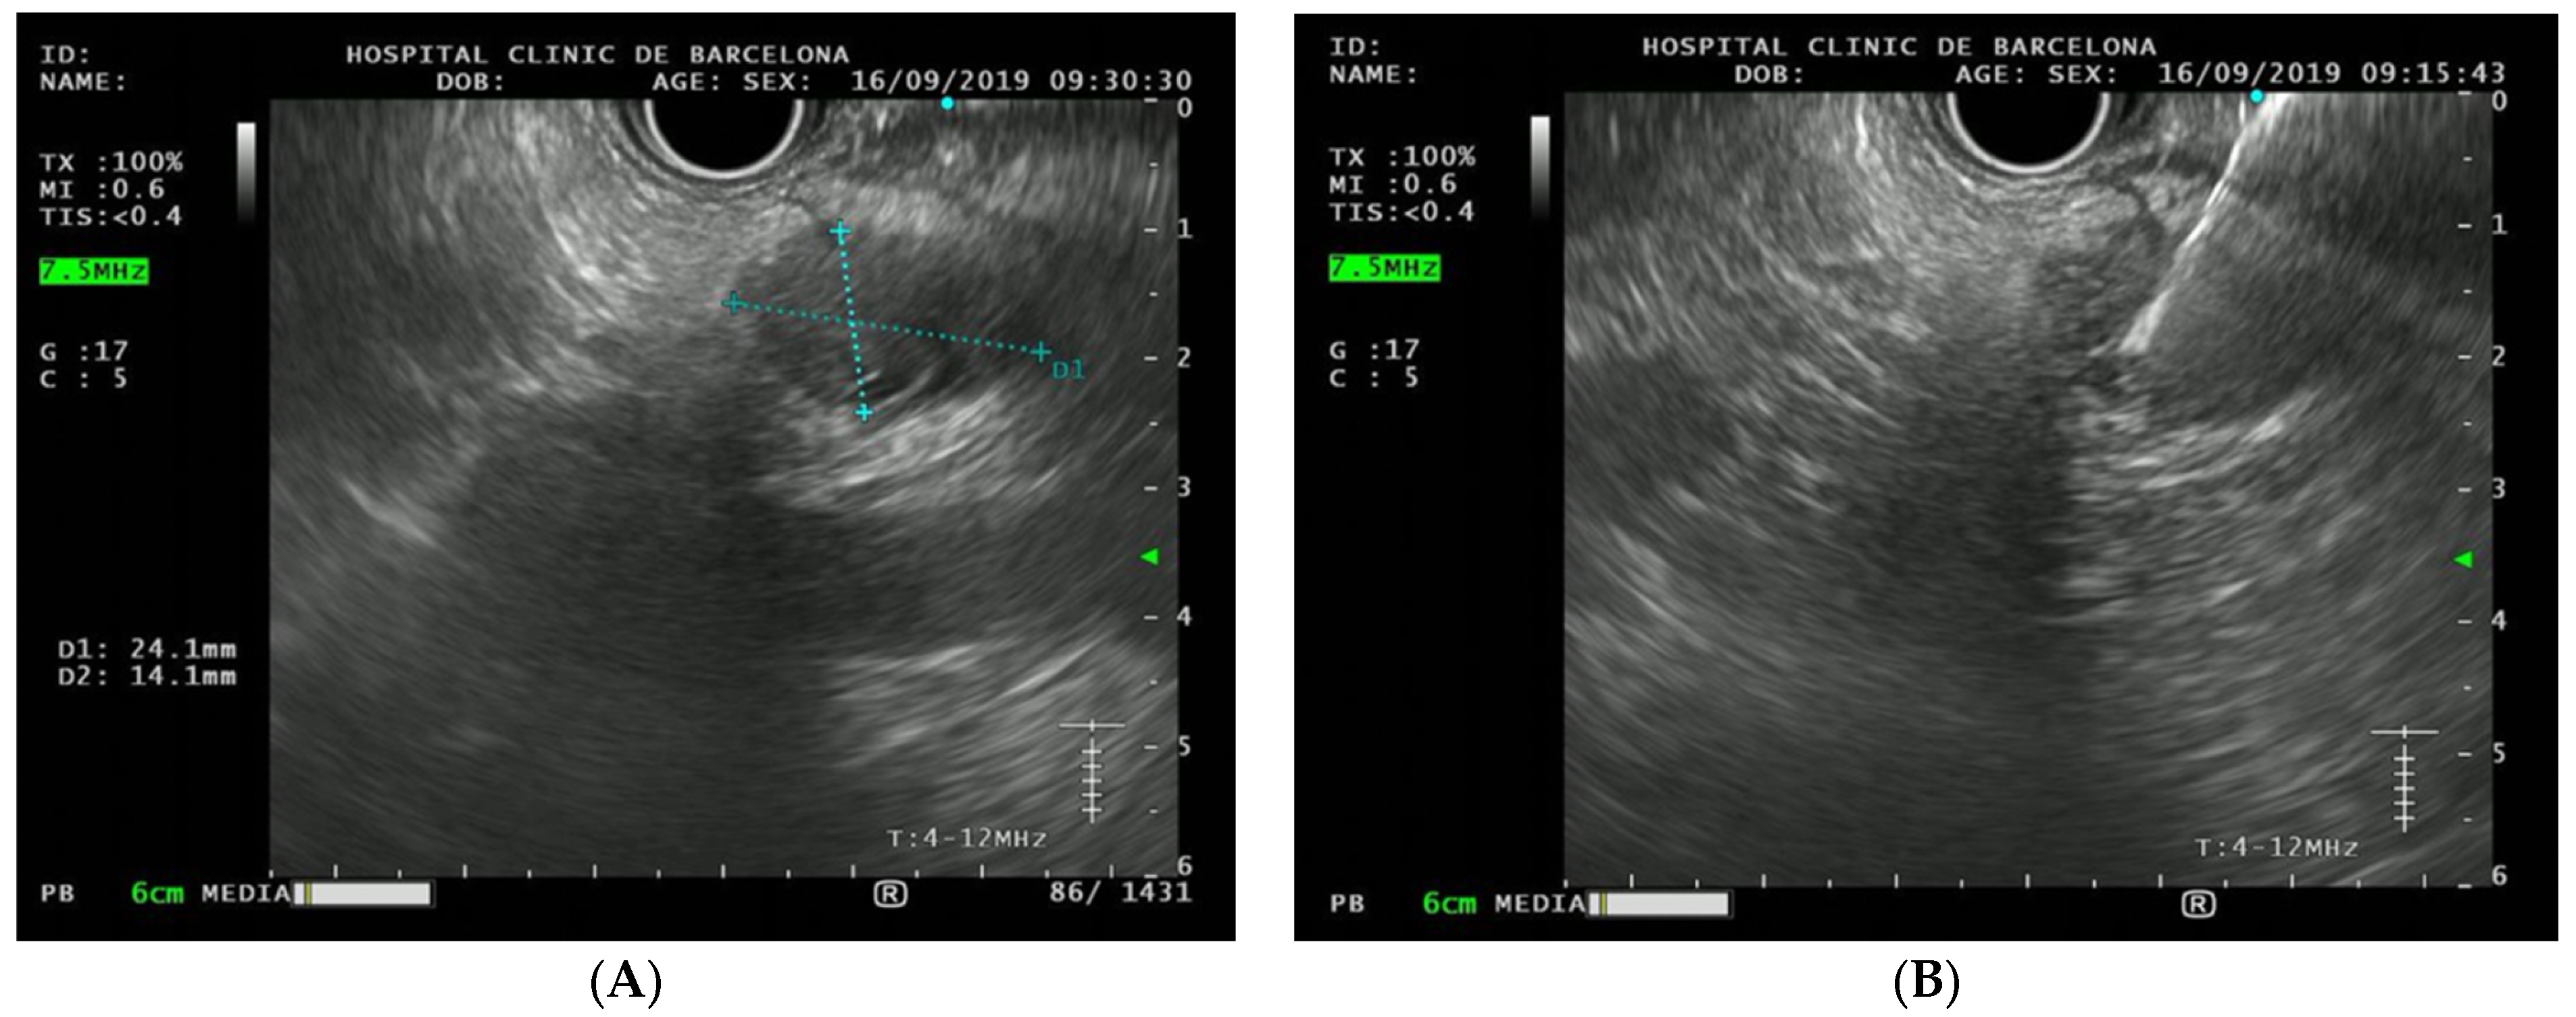

3.2. Pancreatic Cancer Surveillance Program: Characteristics and Findings

| Neuroendocrine tumor | Yes | Yes | Yes | No |

| Neuroendocrine tumor | Yes | Yes | Yes | Yes |

| Neuroendocrine tumor | Yes | Yes | Yes | Yes |